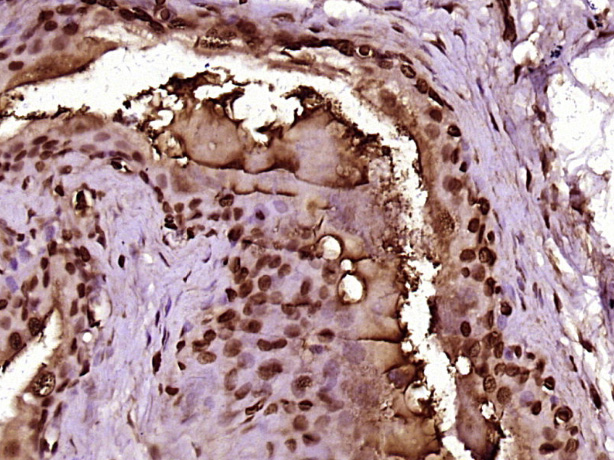

Paraformaldehyde-fixed, paraffin embedded (Rat stomach); Antigen retrieval by boiling in sodium citrate buffer (pH6.0) for 15min; Block endogenous peroxidase by 3% hydrogen peroxide for 20 minutes; Blocking buffer (normal goat serum) at 37°C for 30min; Antibody incubation with (MMP6/MPHOSPH6) Polyclonal Antibody, Unconjugated (bs-17687R) at 1:400 overnight at 4°C, followed by operating according to SP Kit(Rabbit) (sp-0023) instructionsand DAB staining.

Paraformaldehyde-fixed, paraffin embedded (Rat urinary bladder); Antigen retrieval by boiling in sodium citrate buffer (pH6.0) for 15min; Block endogenous peroxidase by 3% hydrogen peroxide for 20 minutes; Blocking buffer (normal goat serum) at 37°C for 30min; Antibody incubation with (MMP6/MPHOSPH6) Polyclonal Antibody, Unconjugated (bs-17687R) at 1:400 overnight at 4°C, followed by operating according to SP Kit(Rabbit) (sp-0023) instructionsand DAB staining.